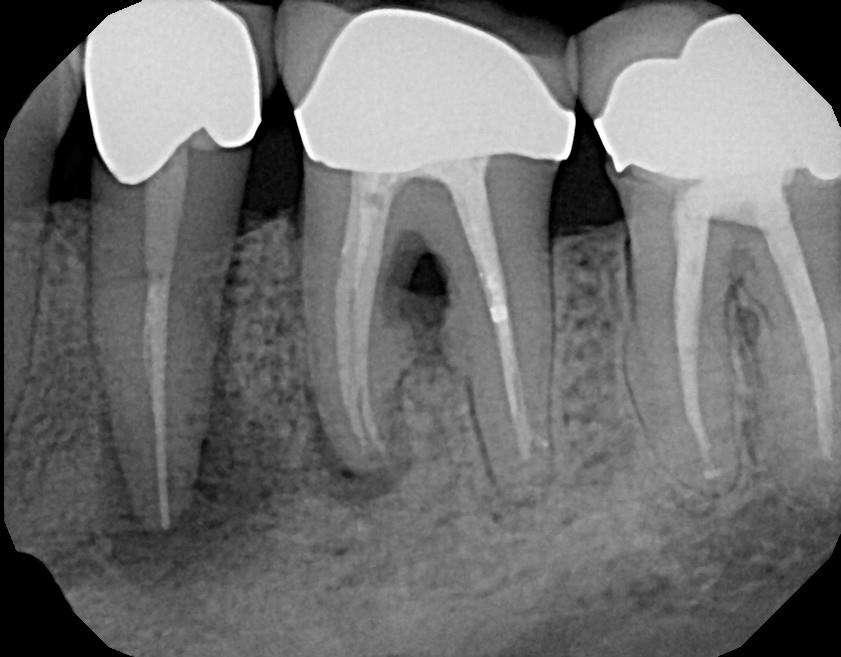

Most certainly in the ground, but only after you separate your human body from the dead body in your mouth, your root cadavers. These you see here are routine pictures of dead teeth:

The pathological tissues such as granuloma, cysts, abscesses, marked acute/chronic inflammation, and necrotic bone, to name a few, are the drainage field of the septic tooth. Nature attempts to prevent toxic dissemination throughout the full biome thus insuring its health, hopefully.

A septic tank analogy is valid here in that the dead tooth or dental implant is a reservoir for corrupt matter and their liquids and gases, leaking out into the underlying bone, lymphatic, blood vascular, neurological tissues—apical tissues.